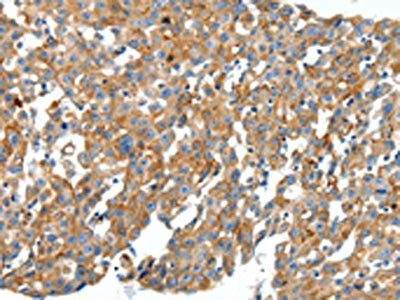

The image on the left is immunohistochemistry of paraffin-embedded Human breast cancer tissue using CSB-PA185715(CXCL12 Antibody) at dilution 1/40, on the right is treated with synthetic peptide. (Original magnification: ×200)

The image on the left is immunohistochemistry of paraffin-embedded Human cervical cancer tissue using CSB-PA185715(CXCL12 Antibody) at dilution 1/40, on the right is treated with synthetic peptide. (Original magnification: ×200)